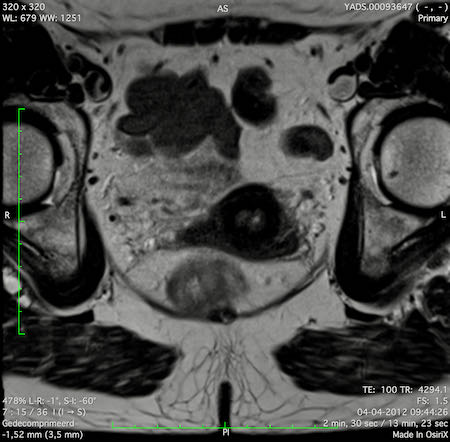

Hình ảnh

Các hình ảnh được cung cấp cho thấy ung thư biểu mô tế bào nhẫn với tình trạng dày lan tỏa thành trực tràng, hình ảnh bia bắn điển hình, và sự xâm lấn mỡ mạc treo trực tràng.